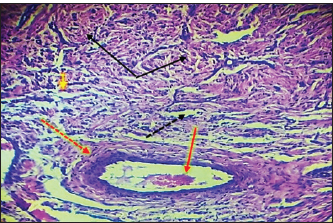

Histopathological evaluationThe zinc gluconate groupIn the GI group, 30 days post-injection, the testes section showed atrophy of the tubuli recti with dilatation of others, desquamation of the tubuli recti epithelium, infiltration of inflammatory cells, and degeneration of seminiferous tubules (Fig. 4). Fibroblast proliferation was observed around the thickened walls of blood vessels (Fig. 5). Other sections showed complete seminiferous tubule stroma necrosis with necrosis in tunica albuginea (Fig. 6). Despite the presence of Leydig cell clusters, some sections displayed germinal cell exfoliation in the lumen of seminiferous tubules accompanied by edematous interstitial tissue and inflammatory cell infiltration (Fig. 7).

Fig. 4. Histopathological section of testes from a dog in the zinc gluconate group at 30 days post-intrasticular injection, showing atrophy of the tubuli recti (black arrow) with dilatation of other (dotted black arrow) , disequilibrium of the tubuli recti epithelium (red head), infiltration of granulation inflammatory cells (red arrow), and degeneration of seminiferous tubules (yellow arrow), (H & E stain 10X).

Fig. 5. Histopathological section of testes from dogs in the zinc gluconate group at 30 days post-intratestinal injactin, showing degeneration of the tubule in the testis recti (black dotted arrow), granuloma (black arrow), congestion (red arrow), thickening wall of blood vessels (red dotted arrow), and proliferation of fibroblasts (yallow arrow),(H & E stain 10X).